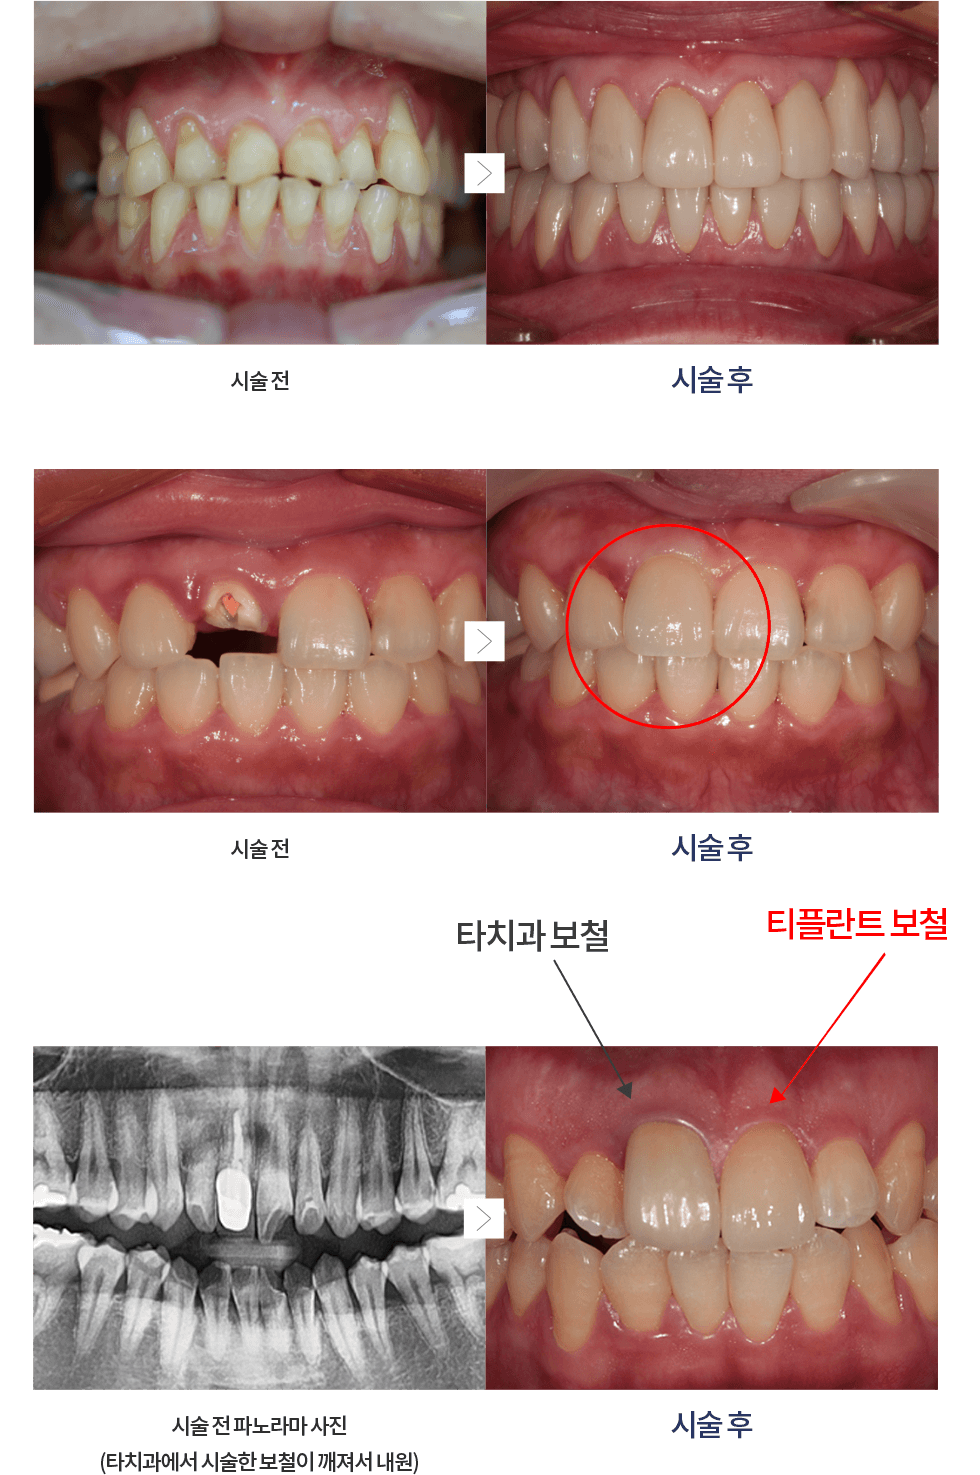

¼¿ïƼÇöõÆ®´Â dzºÎÇÑ °æÇè°ú ³ëÇÏ¿ì·Î ÀÚ¿¬Ä¡¾ÆÃ³·³ ÀÚ¿¬½º·´°Ô

ÀÚ¿¬Ä¡ º»·¡ ¸ð½ÀÀ¸·Î ȸº¹½ÃÄÑ µå¸®±â À§ÇØ ³ë·ÂÇϰí ÀÖ½À´Ï´Ù.